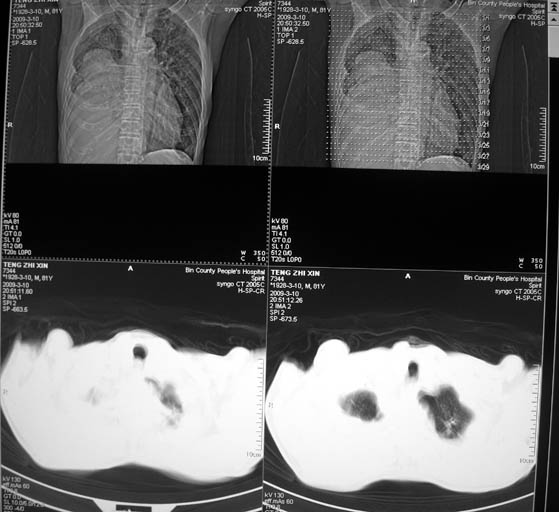

标题: CT18642:男,81岁,发热待查。

男,81岁,发热待查,右侧是占位还是膈疝?

右肺中央型肺癌并胸水。

右肺中央型肺癌并两侧胸水,左肺转移,腹水

1)考虑右肺下叶中央型肺癌并左肺转移。2)两肺上叶结核(陈旧性)。3)双侧胸腔积液。4)腹水。

很明显的排除膈疝。考虑右肺中央型肺癌,建议增强。胸腔恶性胸水。